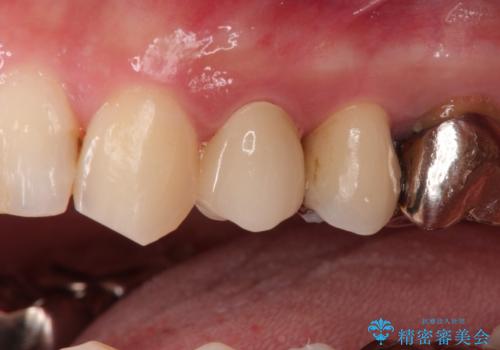

大きい虫歯 根管治療〜オールセラミッククラウン

- 大きな虫歯を認めた患者様です。

自発痛を認めたことから、不可逆性歯髄炎の診断を行い治療を介入しております。

根管治療した場合は速やかに被せ物による修復が必要です。